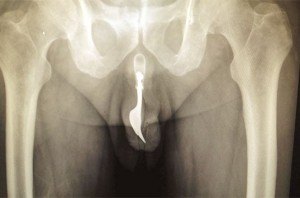

Segundo o urologista Dr. Geraldo F., diretor da Sociedade Brasileira de Urologia, a fratura acontece quando o pênis, em ereção, é submetido a uma pressão axial (na ponta).